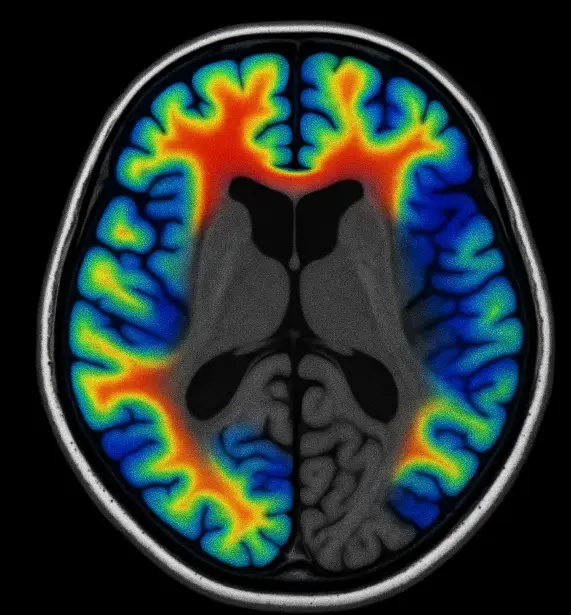

Each participant wore EEG (electroencephalogram) sensors while completing their tasks. This allowed researchers to measure real-time brain activity during the essay-writing process.

- Reduced Brain Activity: The study found that participants using AI tools showed reduced brain activity, particularly in areas associated with memory, critical thinking, and problem-solving.